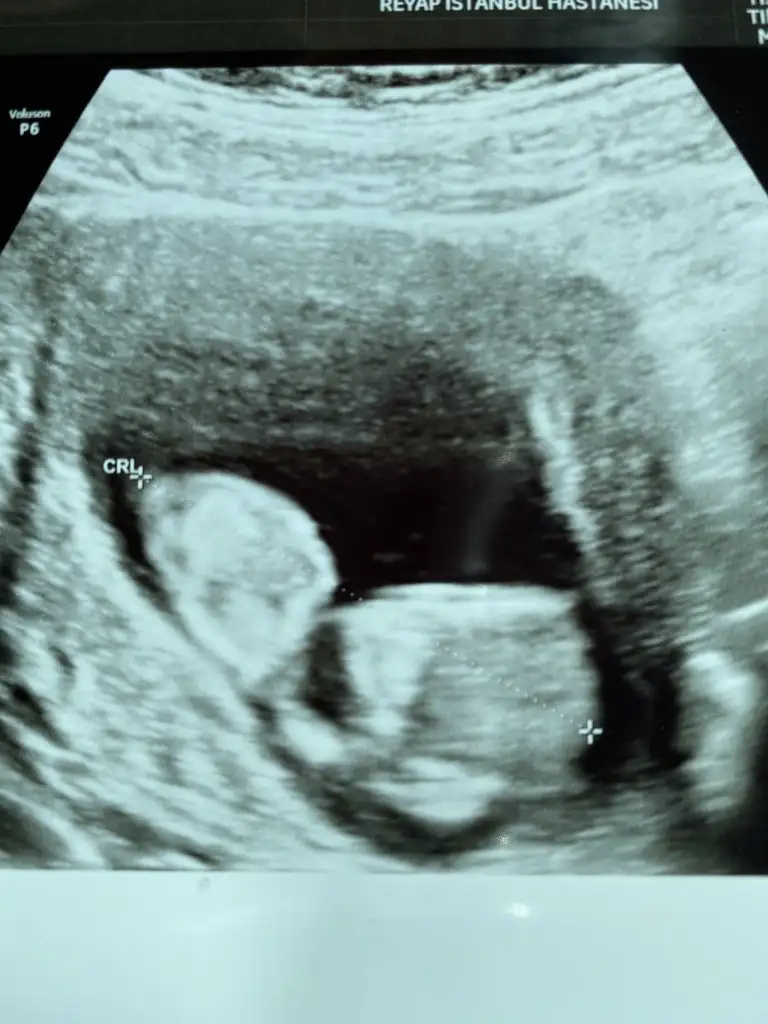

Pek belirgin çıkmamış yaa bilemedim valla. Ama eli ayağı erken belli olur erkeklerde derler hep bunda pek belli değilKızlar cinsiyet tahmini yapabilir misiniz acaba merak ettim, doktora çekindim sormaya açıkçası çok mu erken diye. 11+5 karından bakıldı